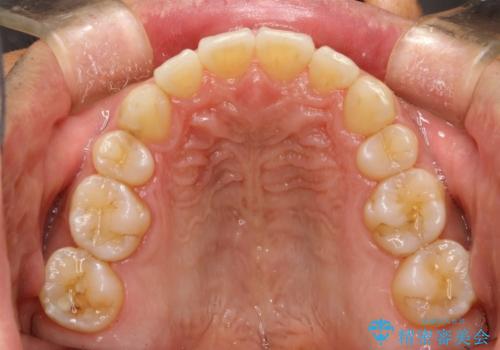

- 以前、上下左右4本抜いてワイヤー矯正をしていた方で、後戻りで下の前歯のガタガタを気にして来院されました。

マウスピース矯正にて、下の歯はIPR(歯と歯の間を削る)を入れることでガタガタの改善、咬み合わせの深さも改善をはかる治療計画をたてました。

歯と歯の間を削って隙間を作って矯正をしています。

保定装置(後戻り防止のための装置)は、基本的にはマウスピースタイプをお渡ししているのですが、患者様のご希望で取り外ししないタイプを希望されたので、前歯の裏側を細いワイヤーで固定(ボンディングリテーナー)を作成しています。